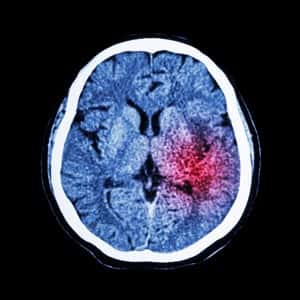

There are two different types of brain attack, both involving the blood vessels to the brain. In Dr. Taylor’s case, the blood vessels broke open and bled into the brain. Such a hemorrhagic stroke is less common, but it can be even more damaging than an ischemic stroke caused by a blood clot in an artery serving the brain. Such blood clots account for 87% of strokes. Thus, reducing the likelihood of blood clots is an important step to reducing the risk of a brain attack.

Bleeding and clotting tend to cause similar symptoms, but determining the type of stroke is crucial. Once a person shows up at the emergency department, the staff there will arrange a CT scan to see what is happening. For a stroke caused by a clot, an anticoagulant can be very useful, but it would be exactly the wrong thing for someone who is already bleeding. If the problem is a clot, the image should tell the doctors where it is. There is now a device that can be threaded into the blood vessels to fish the clot out. This approach is showing great promise. Another treatment is for people with Afib to prevent them from forming clots. It is a surgical procedure called a left atrial appendage closure that eliminates a pocket in the heart where blood tends to pool before it clots.